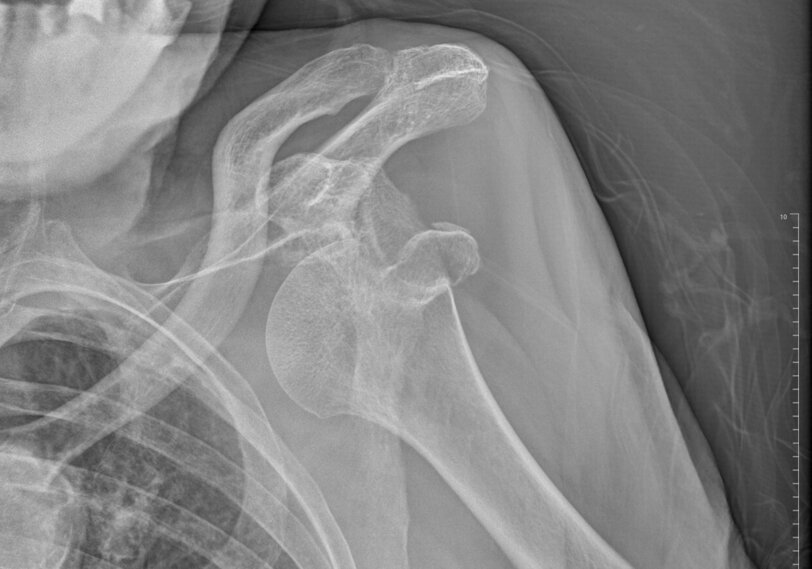

ARTROSI GLENO-OMERALE

a0ea054ae91a1c769749d163249d2c2a2dea7ffd.jpeg

Diversi fattori possono concorrere al deterioramento della regolarità e della congruenza delle strutture ossee e cartilaginee della spalla. Le due articolazioni maggiormente coinvolte sono la gleno-omerale e la acromion-clavicolare. A seguito di tali processi degenerativi, si crea una erosione della cartilagine che ricopre tali strutture, con conseguente danno delle strutture ossee sottostanti e dei tessuti molli circostanti. Questo comporta una perdita di congruenza dei capi ossei con conseguente progressiva limitazione dell'articolarità associata a dolore.

La patologia degenerativa articolare a livello dell'articolazione gleno-omerale (GO), può essere di tipo concentrico o eccentrico. La prima forma è in genere di natura idiopatica, cioè dovuta ad una precoce usura delle strutture cartilaginee dovuta o al passare degli anni o alla presenza di patologie associate, quali forme artritiche sistemiche (ad es. Artrite Reumatoide), o patologie vascolo-nervose ( ad es. diabete, patologie nervose periferiche, esiti di terapie croniche con cortisonici). La forma degenerativa eccentrica invece è generalmente secondaria ad una alterata meccanica articolare, con conseguente usura patologica delle strutture articolari e tendenza alla risalita della testa omerale verso la volta acromiale. Le lesioni massive della cuffia dei rotatori, esiti di traumi, di fratture o di precedenti interventi chirurgici sono di solito alla base di questo tipo di artrosi. Le alterazioni dell'articolazione acromion-clavicoalre (AC) possono essere anch'esse di natura idiopatica, legate cioè ad un "naturale" processo degenerativo del disco fibrocartilagineo che si trova interposto fra queste strutture, o più spesso conseguenza di traumi a livello di tale articolazione (lussazioni acromion clavicolari di I - II grado). Un accurato esame clinico e uno studio radiografico sono sufficienti per fare una diagnosi certa. La risonanza magnetica può mostrare meglio i rapporti dell'articolazione con il sottostante spazio subacromiale.